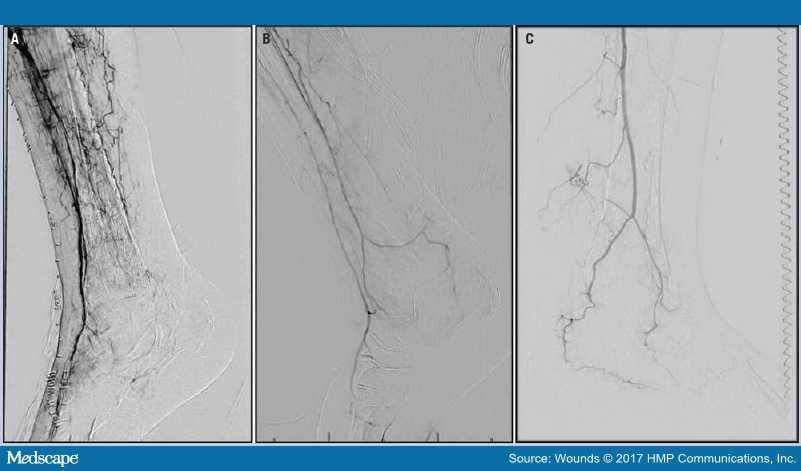

Unfortunately, however, such screening tests may be misleading in patients with heel pressure injuries when the ABI does not provide direct information about perfusion of the rearfoot. By convention, the ABI represents a mathematical ratio with the systolic pressure in the brachial artery as the denominator and the systolic pressure of an ankle artery as the numerator (the higher value of the anterior tibial artery [ATA] or posterior tibial artery [PTA] is used).[13–15] Figure 1A demonstrates a patient with single-vessel arterial runoff through the ATA without any direct or indirect inflow to the heel. It is likely the ABI would be calculated based on the ATA in this situation, and it might even appear normal, even though the heel is ischemic. This concept may be best described by the so-called "orphan heel syndrome," in which the only arterial inflow to the foot is via the ATA, essentially leaving the plantar rearfoot in an ischemic zone.[16]

Figure 1.

Three angiograms demonstrate situations involving heel tissue loss in which noninvasive vascular testing and the ankle-brachial index (ABI) may be misleading. (A) A patient with only anterior tibial artery runoff into the foot without any direct or indirect perfusion of the heel. Because the ABI ratio is conventionally calculated using the higher of the anterior tibial or posterior tibial artery values, it is possible a normal pressure and ratio could be calculated based on the anterior tibial artery, even though there is no perfusion to the heel; (B) a patient with antegrade flow through the anterior tibial and peroneal arteries. The primary flow to the heel is likely via the peroneal artery, which is not generally measured with ABI; and (C) a patient with only peroneal artery single-vessel runoff, which would not likely be measured with the ABI.

Further, Attinger et al[24] have described the arterial supply to the heel, with the angiosome theory as a redundant dual inflow via the posterior tibial and peroneal arteries. Measurement of the peroneal artery is not included in calculation of the ABI, although the peroneal artery is the infrapopliteal vessel most likely to be spared of chronic obstructive atherosclerotic disease.[25,26] Figure 1B demonstrates a clinical situation in which the primary arterial flow to the heel is likely through the peroneal artery, but where the ABI would conventionally be calculated based on the ATA. Figure 1C represents a patient with only single-vessel runoff through the peroneal artery. It is unclear what information, if any, the ABI would provide in this situation given the lack of measurement of the peroneal artery pressure in the formula.